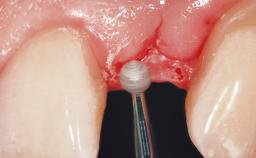

For soft tissue management, the initial healing caps are replaced with a longer type 8 weeks after implant placement in a second intervention before prosthodontic treatment is initiated.